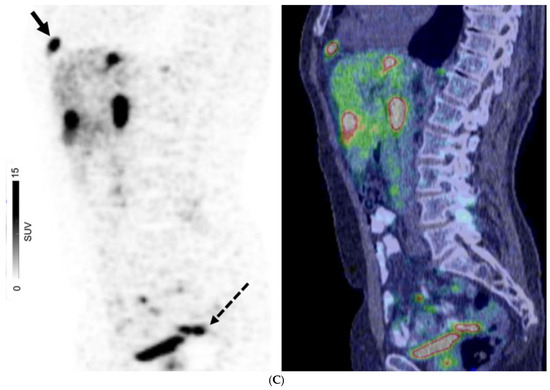

Figure 2.

A 67-year-old man with well-differentiated G1 small bowel NET, Ki 67 = 3% metastatic to liver. Staging CT showed mid-ileal tumor, regional nodal metastases, and bilobar liver metastases [CT stage: n1M1a]. 68Ga-DOTATATE PET/CT (A,B) Axial and Coronal—CT (left), fused PET/CT (middle) and PET (right); (C) Sagittal—Fused PET/CT (left) and PET (right) shows in addition, extrahepatic metastases including extraregional nodes including supraclavicular and cardiophrenic nodes (arrows in (A,C)), and peritoneal metastases (dotted arrows in (B,C)); overall, PET stage: n1M1c.

For patients with GEP NETs, no distant metastases (M0) were observed on both CI and PET in 186/369 (50.4%) of patients. There were 83 patients with GEP NETs who had discordant M-stage on CI and PET, in which PET suggested a higher stage in 75/83 patients (90.4%) and lower stage in 8/83 (9.6%) (Figure 2). For those with GEP NETs, extrahepatic metastatic disease was identified by PET in 42/114 (36.8%) patients where CI showed only liver metastases (M1a) (Figure 3).